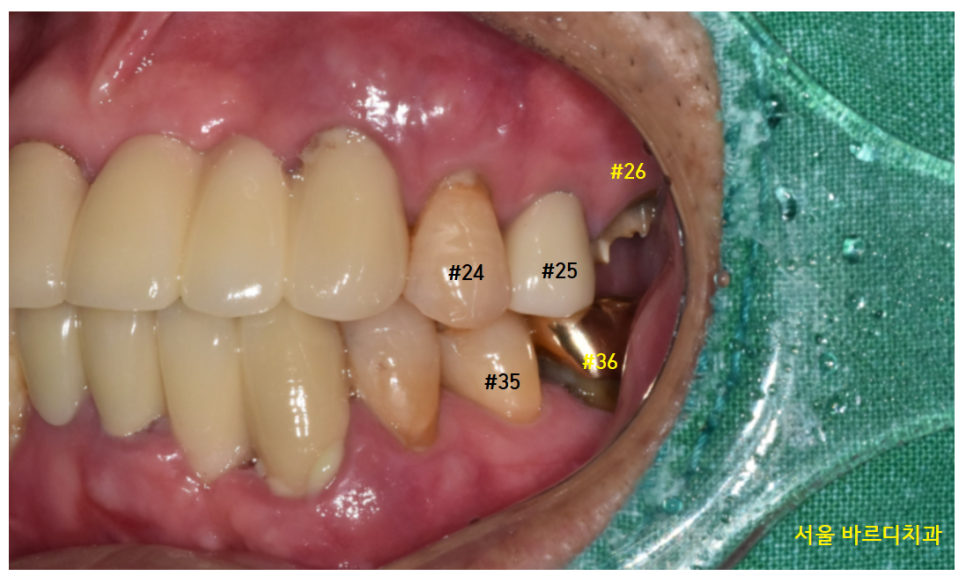

여기서 궁금하실 겁니다.

윗니 맨 끝에 치아 말고

다른 부위 치아는 그대로 두면 안 되나요..?

씹는데 불편하지는 않아서요..

암사동 치과 케이스 사진 한 장으로 설명드릴게요~~

23.02.12

다른 부위의 경우 양옆에 치아들이 있죠~

그러다 보니...

치아를 발치하고 그대로 두게 되면

치아가 없는 쪽으로

쓰러지게 됩니다.

그리고 매일 딱딱딱 닿던 것이 없어지니

치아가 빠진 쪽으로 솟구치기도 하고요.